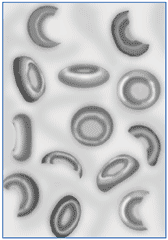

La anemia hemolítica es un grupo de trastornos hemolíticos (sea intravascular como extravascular), que causan la disminución de la masa de glóbulos rojos sanguíneos. A diferencia de anemias no hemolíticas (por déficit de hierro por ejemplo), en las anemias hemolíticas la vida de los glóbulos rojos en sangre periférica (normal entre 90 y 120 días) está acortada.